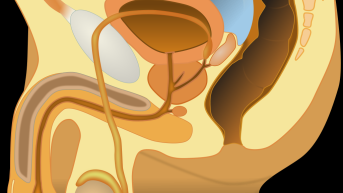

Os médicos aconselham a utilização dos remédios para engravidar em mulheres que tem ovulação irregular ou que tem ausência total da ovulação. Obviamente após investigação do casal, no caso da mulher com ultrassonografias para verificação de obstrução de trompas e o homem espermograma para verificação da qualidade do sêmen.

Em alguns casos, quando o tratamento através de remédios para engravidar não se obtém sucesso esperado, só é possível reverter à infertilidade através de cirurgias ou até mesmo apelando para os métodos de reprodução assistida, como a inseminação artificial e a fertilização in vitro. A infertilidade pode ocorrer por vários fatores:

Para Mulheres: Anatômicos, imunológicos e casos de endometriose. Alterações hormonais, amenorreia (períodos sem menstruação), falta de ovulação ou ovulação de ovócitos imaturos ou com má formação.

Homens: Ausência total ou parcial de espermatozoides, alteração da forma ou quantidade de espermatozoides fazendo um espermograma. O diagnóstico do homem é mais fácil de ser realizado, então é aconselhado por especialistas que seja investigado em primeiro lugar, antes de ser dado inicio no tratamento da mulher.